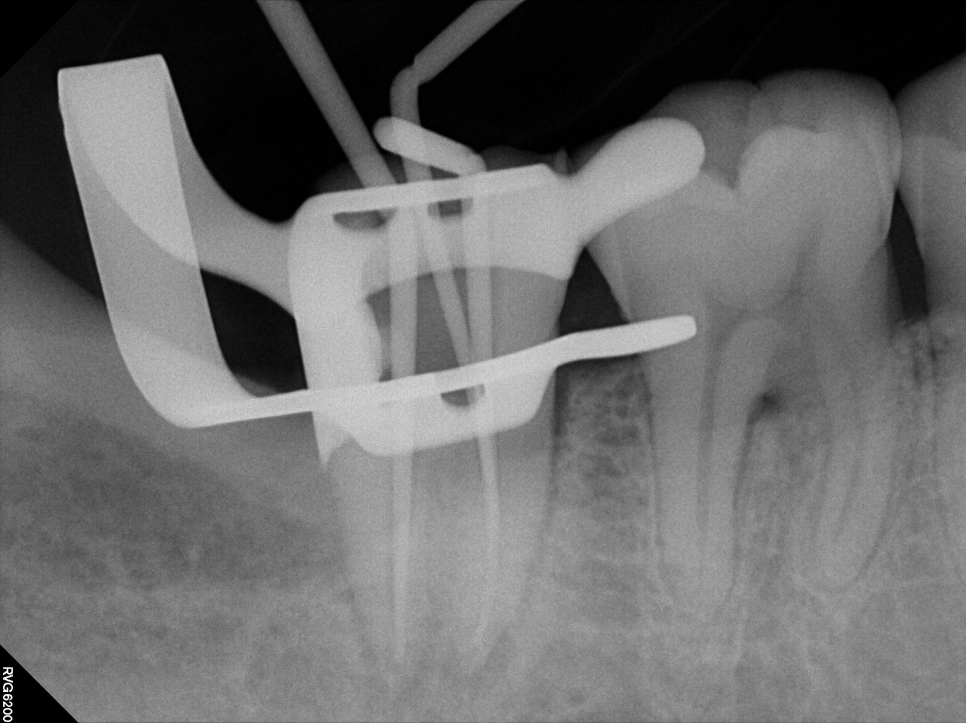

✅ 현미경 신경치료

미세현미경을 통해 눈으로 보이지 않는 작은 신경관까지 치료

불필요한 손상을 줄이고 재발 위험 최소화

치아 내부를 정밀하게 보존

과정을 쉽게 이해하실 수 있도록 준비한 참고 이미지입니다.

촬영일:2025.08.14